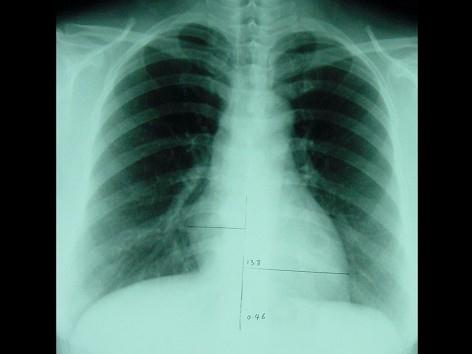

此心脏正位片描述正确的是 ( )A、“普大型”心脏B、“二尖瓣型”心脏C、“中间型”心脏D、“横位型”心脏E、“主动脉瓣型”心脏

问题 此心脏正位片描述正确的是 ( )

选项 A、“普大型”心脏 B、“二尖瓣型”心脏 C、“中间型”心脏 D、“横位型”心脏 E、“主动脉瓣型”心脏

答案 C